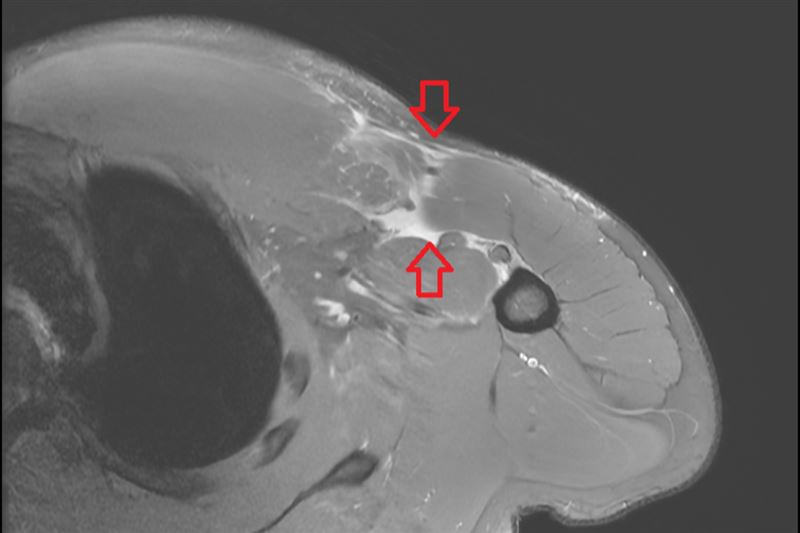

個案核磁共振檢查發現其右側胸大肌斷裂。(圖.台北慈濟醫院提供)

如何檢查與治療?李奕澄說,醫師會先透過病史詢問與理學檢查,觀察胸型輪廓、瘀青分布、肌力變化與肌腱走向,並進一步以核磁共振檢查確認斷裂位置與程度。治療方式需依病人狀況綜合評估,對於部分撕裂、功能需求不高的病人,可先採取保守治療,如休息、止痛藥物與復健訓練;但若為急性期完全斷裂,手術通常能帶來較佳的力量與外觀恢復。重要的是,病人手術後需依照醫師指引進行復健,整體而言,胸大肌修復後多數病人可望半年內回到運動或工作,但實際時程仍需視受傷程度與復健遵從性而定。

如上述個案藉由理學檢查與核磁共振影像,診斷為右側胸大肌斷裂,隨即安排胸大肌肌腱縫合手術,固定斷裂肌腱。術後林先生按時復健,力量逐步回升,半年後也恢復日常生活。